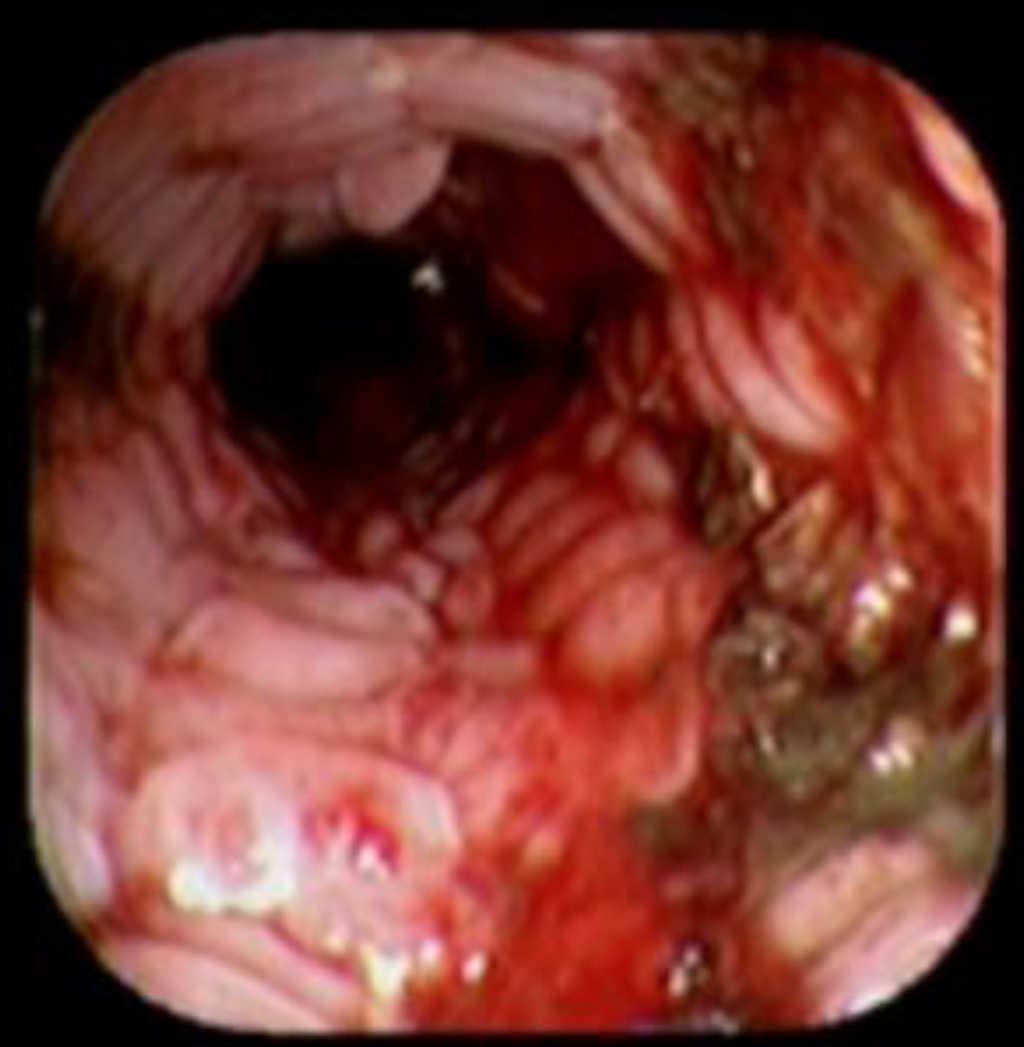

Case reportA 41-year-old man underwent elective laparoscopic Heller myotomy for achalasia; during the procedure a perforation of the esophageal wall was observed, and primary closure of the defect was attempted. The patient started with PO on day three, but he complained of chest pain and fever. Immediately CT scan with oral contrast was performed. A free leakage at esophago-gastric junction was observed. A 15 cm PSEMS (Ultraflex esophageal NG covered (120 mm) stent, Boston Scientific, Natick, MA) was placed across the defect, leading to the distal 1.5 cm non cover into the stomach and the proximal 1.5 cm non cover at 30 cm from incisor (Figure 1). A control CT scan with oral contrast showed good position of the stent, without evidence of leakage. The patient's clinical status improved and began to swallow normally, but showed numerous episodes of reflux despite PPI use. We leave the PSEMS for 26 days beside the reflux symptoms. During the endoscopic procedure to remove the stent the presence of tissue embedding along the covered portion of the PSEMS was noted (Figure 2). The stent was pulled out with an alligator forceps with out major complications and the cover of the PSEMS was seen to be totally destroyed (Figure 3).

Figure 2. The image shows the presence of tissue embedment along the covered portion of the PSEMS.